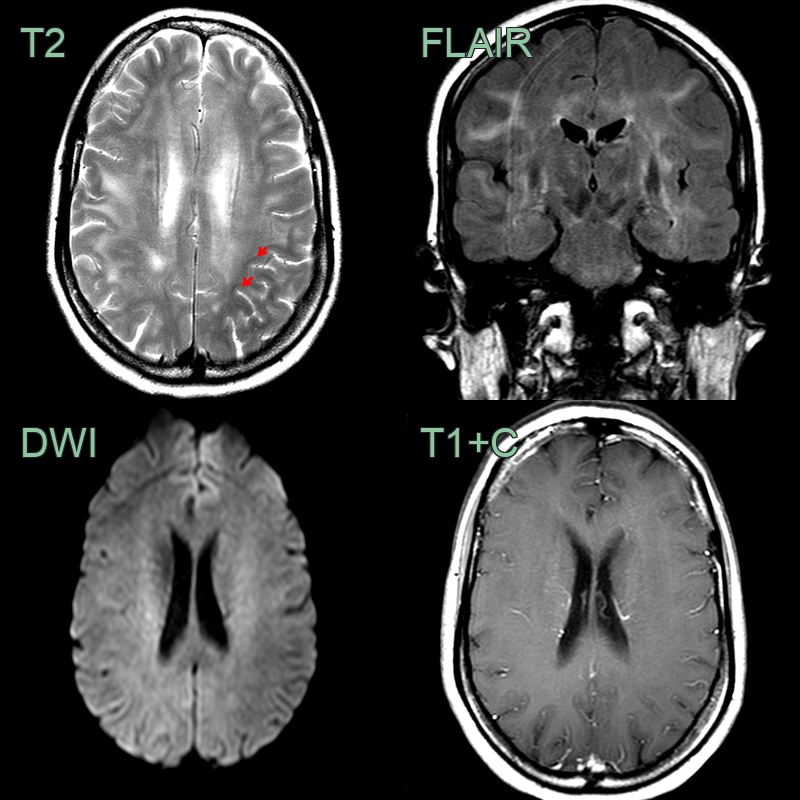

- A 50-year-old patient presented with cognitive impairment.

- A new diagnosis of HIV was made on admission.

- MRI showed patchy diffse white matter hyperintensity without enhancement in both cerebral hemispheres that spared the subcortical U fibres (red arrows).

- Following CSF analysis to exclude other causes and a follow-up scan 1 month later that showed no changes, the findings were ascribed to HIV encephalopathy.